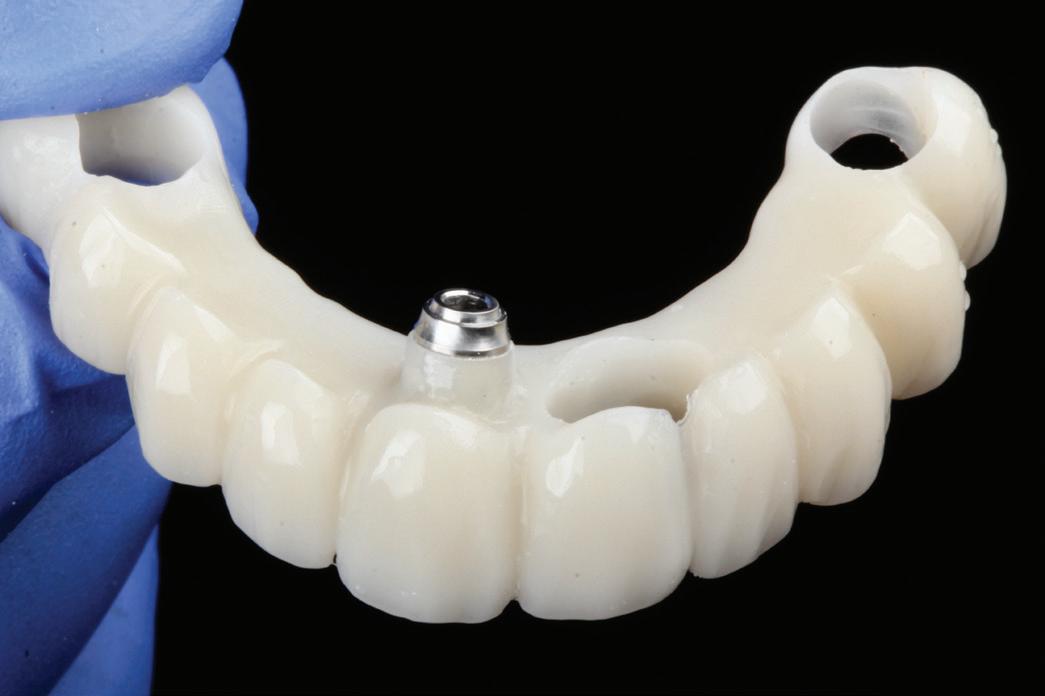

PROSTHETICALLY DRIVEN PLANNING

Tehnologia digitală redefinește terapiile implantare

• Chirurgia implantară cu cea mai inteligentă planificare și mai precisă execuție va necesita în continuare un finisaj protetic care funcționează biomecanic și realizează o estetică naturală ideală individuală. Dacă există un aspect al tratamentului protetic cu provocări în era digitală, acesta ar consta în munca artistică minuțioasă a ceramistului, cu modelarea și pictarea dinților pentru a imita natura.

Colaborarea profesională și planificarea ghidată protetic sunt esențiale pentru rezultate predictibile de succes.